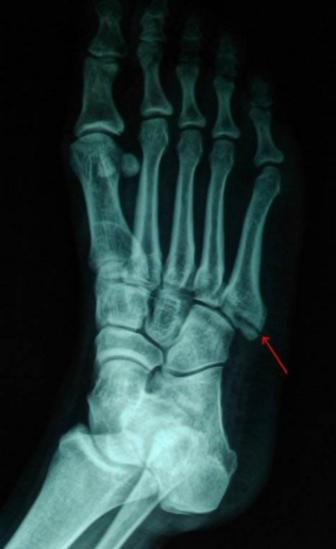

跖骨(足中间的骨)的骨折很常见,因行走过多或过度劳损造成,也可因突然、强大的*力暴**冲击所致。这种骨折易发生在老人和热爱运动的年轻人身上。

跖骨(足中间的骨)的骨折